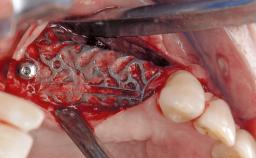

Resective Surgical Treatment of Peri-Implantitis Including Implantoplasty

In this case, Myroslav Solonko, Ignacio Sanz Sánchez and Mariano Sanz present a treatment that aims to eliminate exposed implant threads by modifying the implant surface, converting a moderately-rough surface into a smooth surface.